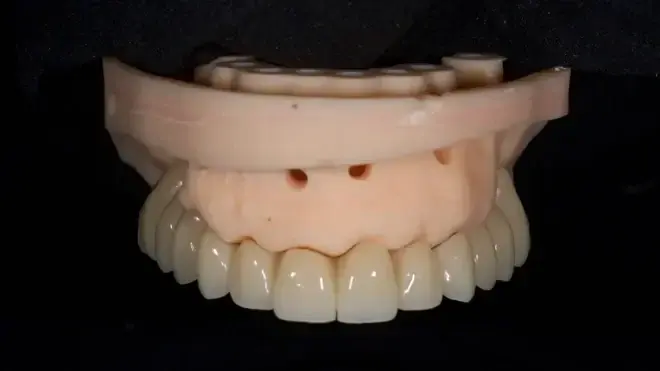

При последната среща беше поставена окончателната хибридна винтово-фиксирана протеза. Окончателната протеза се състоеше от CAD/CAM титанова рамка, завинтена към всички импланти, и три монолитни циркониеви протезни сегмента, залепени отгоре (фиг. 18а–в). Беше оценена оклузията и пациентът беше включен в четиримесечна програма за поддържане. При последната контролна визита (една година след поставянето на имплантите) всички импланти бяха успешни и пациентът беше удовлетворен от новата протеза (фиг. 19–22).

Фиг. 18а–в: Хибридна окончателна протеза, състояща се от CAD/CAM титанова лента и три циркониеви протезни сегмента, залепени отгоре.